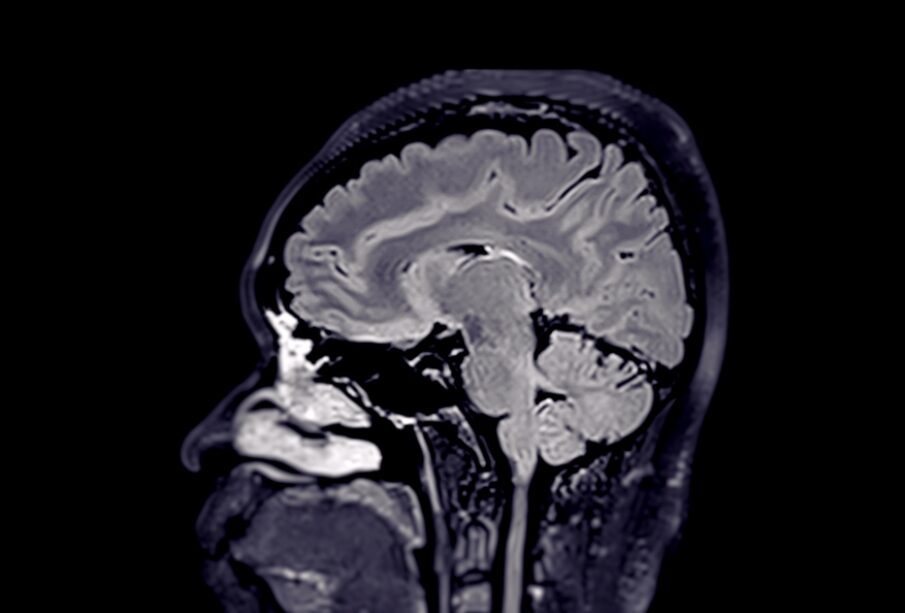

Žmogaus smegenyse yra sudėtinga, skysčiu užpildytų ertmių sistema, žinoma kaip skilveliai. Šis vadinamasis skilvelių tinklas susideda iš porinių šoninių skilvelių, trečiojo ir ketvirtojo skilvelio bei vandentiekio, jungiančio juos tarpusavyje. Visuose juose cirkuliuoja smegenų skystis – cerebrospinalinis skystis (CSS), kurį gamina specializuotos struktūros, vadinamos kraujagysliniu rezginiu.

Trečiasis skilvelis – tai siaura, piltuvo formos ertmė, esanti galvos smegenų centre, tarp abiejų tarpinių smegenų pusrutulių. Jis užima centrinę smegenų dalį ir atlieka svarbų vaidmenį užtikrinant ryšį tarp visų kitų smegenų skilvelių.

Skilvelis išsidėstęs ties vidurine galvos smegenų linija, tarp abiejų smegenų pusrutulių, iš karto tarp dešiniojo ir kairiojo gumburo. Viršuje yra dvi išsikišusios kišenės – supraoptinis išsišakojimas (virš regos kryžmės) bei infundibulinė kišenė (virš regos nervo stiebo).

Trečiasis skilvelis jungiasi su šoniniais skilveliais per Monro angas, o su ketvirtuoju skilveliu – per Silvio vandentiekį. Šie kanalai užtikrina nuolatinę skysčio cirkuliaciją visoje skilvelių sistemoje.